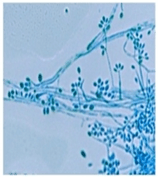

| Conidiophores and conidia | |

When in the environment or grown in the laboratory at 25 °C (77 °F) S. schenckii assumes its hyphal form.[5] Macroscopically, filaments are apparent and colonies are moist, leathery to velvety, and have a finely wrinkled surface. The colour is white initially and may change color over time to become cream to dark brown (“dirty candle-wax” color).[2] Microscopically, hyphae are septate approximately 1 to 2μm in diameter. Conidia are oval shaped and glass like (hyaline) in appearance. They may be colorless or darkly colored. Conidia are sometimes referred to as resembling a flower.[6]